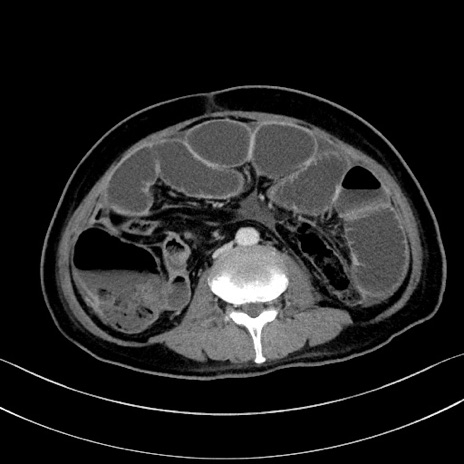

症例28(横断像)

【症例】60歳代男性

【主訴】嘔吐

【現病歴】胃癌にて胃全摘後。食思不振が悪化し、夜中に嘔吐することがある。

【既往歴】胃癌、胃全摘、脾摘、胆摘後

【データ】WBC 5900、CRP 10.56